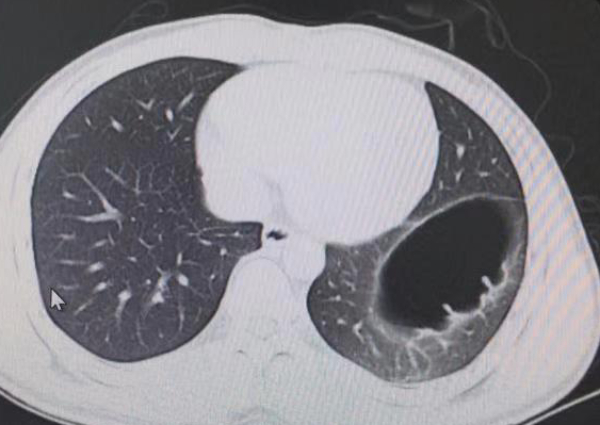

Ảnh chụp cắt lớp vi tính cho thấy thoát vị cơ hoành của Mai.

Trước sự ngạc nhiên của anh, bác sĩ nhanh chóng chẩn đoán và phát hiện ra anh bị thoát vị cơ hoành bẩm sinh. Điều này xảy ra khi cơ hoành ngăn cách ngực với bụng, có một lỗ mở cho phép các cơ quan bụng di chuyển lên trên ngực.

Trong trường hợp của Mai thì anh bị bẩm sinh, khiếm khuyết này đã có từ lúc sinh ra.

Bác sĩ Feng Jinhang đã quan sát và nghe thấy âm thanh kỳ lạ trong ruột của anh, điều này đúng như phỏng đoán ruột đã di chuyển lên ngực. Anh cần phải thực hiện một cuộc phẫu thuật để di chuyển các cơ quan nội tạng về đúng vị trí và sửa chữa lại cơ hoành.

Thoát vị cơ hoành có thể gây hoại tử đường tiêu hóa, thủng và nhiễm trùng đe dọa tính mạng nếu không được điều trị, do đó cần phải được chăm sóc y tế ngay lập tức.